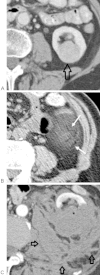

Although percutaneous ablation of small renal masses is generally safe, interventional radiologists should be aware of the various complications that may arise from the procedure. Renal hemorrhage is the most common significant complication. Additional less common but serious complications include injury to or stenosis of the ureter or ureteropelvic junction, infection/abscess, sensory or motor nerve injury, pneumothorax, needle tract seeding, and skin burn. Most complications may be treated conservatively or with minimal therapy. Several techniques are available to minimize the risk of these complications, and patients should be appropriately monitored for early detection of complications. In the event of a serious complication, prompt treatment should be provided. This article reviews the most common and most important complications associated with percutaneous ablation of small renal masses.